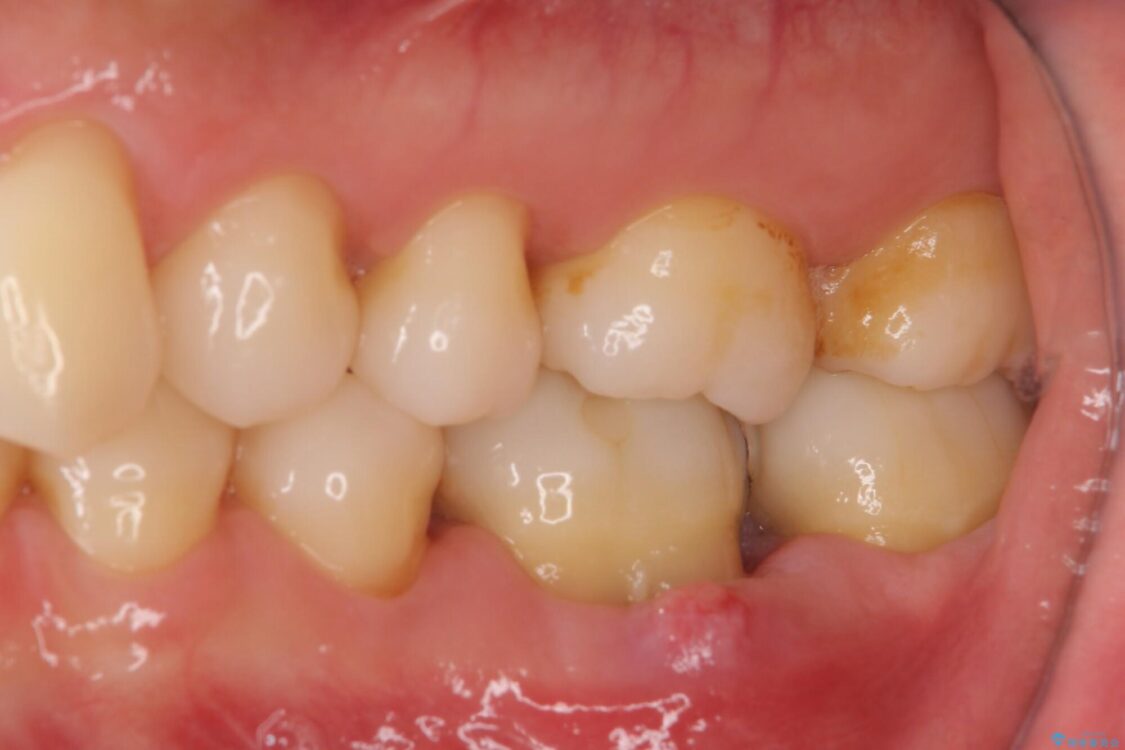

以前他院にて処置をした歯の歯肉からの出血するとのことで来院された患者様です。

治療前

• むし歯で歯茎から血が出てくる オールセラミッククラウンでの補綴治療 治療前画像